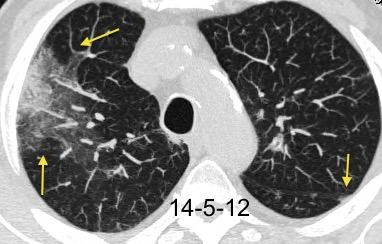

NEUMONITIS POR RADIACIÓN

Neumonitis evidente de 4-12 semanas después de terminar RXT. Fibrosis evidente en 3-4 meses. Estable de 912 meses.

Ca. de mama izquierda. 3/7/09 Radioterapia

La lesión típicamente limitada al campo de irradiación.

Müller NL. 2010

Induce neumonitis. “Tangential beam” para pared torácica.

Jung JI et al. Thoracic Manifestations of Breast Cancer and Its Therapy. Radiographics 2004